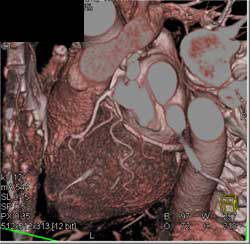

Diagnosis

Normal LAD